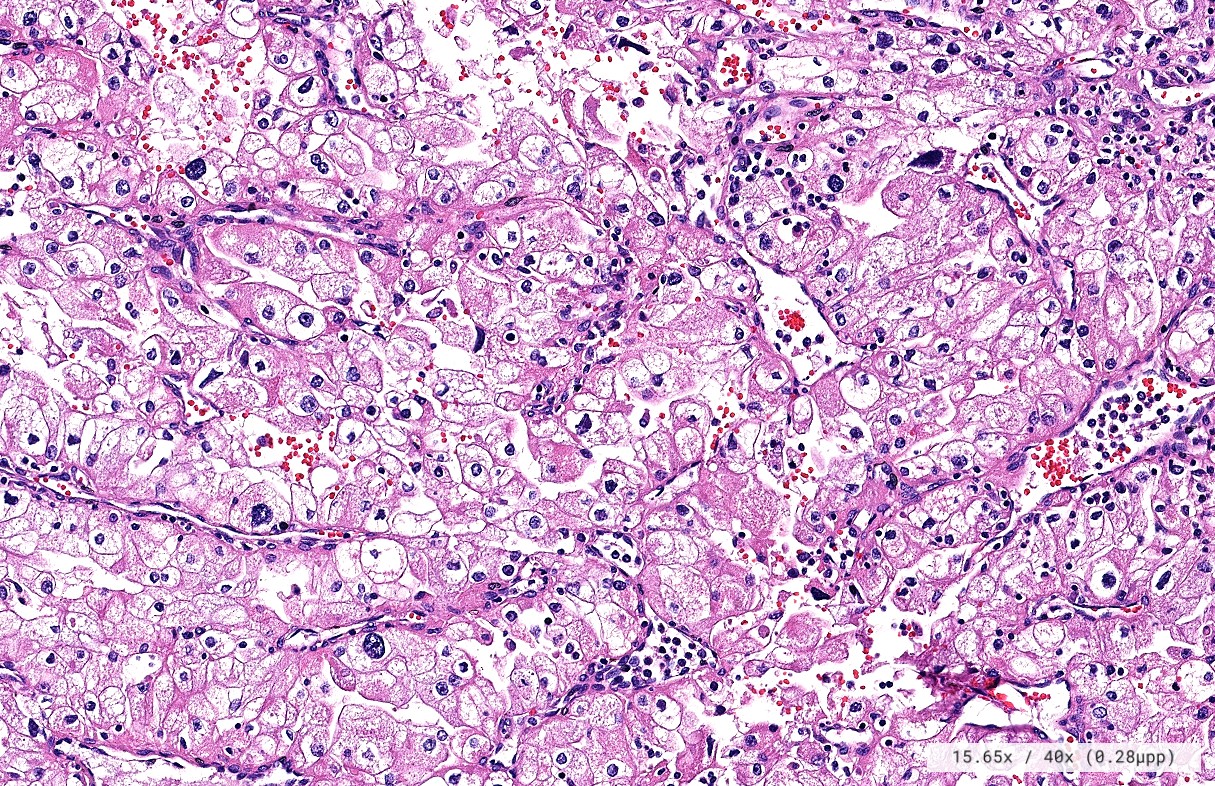

El diagnóstico sobre muestras de tejidos y líquidos corporales en plena era de la medicina del futuro, está basado en la integración de técnicas y conocimientos diferentes.

Hoy más que nunca es importante integrar una buena historia clínica con un correcto estudio de imagen y una buena morfología que además puede estar apoyada con proceso especiales complementarios relacionados con la Inmunología, Biología Molecular y Citogenética, generando así un estudio integral conocido como Patología Molecular.